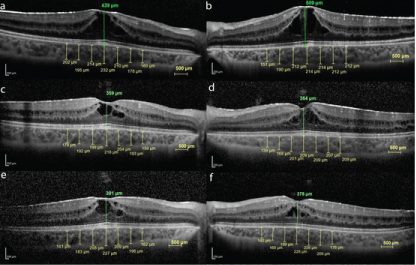

Figure 1: Fundus photography images of the case. View Figure 1

The macular thickness (MT) and ChT was measured by the SD-OCT (Heidelberg Engineering, Heidelberg, Germany) and it repeated in each monthly visit of the patient. Choroidal thickness was measured perpendicularly from the outer edge of the retinal pigment epithelium to the choroid-sclera boundary at the fovea. Central and at six more points which are located at, respectively, 500 μ nasal to the fovea, 1000 μ nasal to the fovea, 1500 μ to the fovea, 500 μ temporal to the fovea, 1000 μ temporal to the fovea and 1500 μ temporal to the fovea were noted. The average of these 7 measurements was taken. Choroidal thickness measurements were made by two masked ophthalmologists (FMA and HO). The average of these two measurements was taken.

On the patient's first exam, the MT was measured 439 μ on his RE and 509 μ on his LE. The average ChT were 198.7 μ on the RE, 200.7 μ on the LE (Figure 2a and Figure 2b).

Figure 2: The OCT images of the case. View Figure 2

At the 3rd month of the management, even the plasma and urine ornithine level was detected dramatically decreased at 702.05 μmol/L and 934.81 μmol/g Kre consecutively. His visual acuities in each eye were improved to RE 20/32, LE 20/25. Macular thicknesses were decreased on the RE to 359 μ and the LE to 364 μ. And the average ChT were also decreased on the RE to 192 μ and on the LE to 191.7 μ (Figure 2b, Figure 2c and Figure 2d). On 6th month of the follow-up, BCVA was found decreased, as same level at the baseline (20/40 in the RE, and 20/32 in the LE). Macular thicknesses were increased on the RE to 391 μ and the LE to 378 μ. And the average ChT were also increased on the RE to 195.1 μ and on the LE to 193 μ (Figure 2e and Figure 2f). Plasma ornithine level was detected at 900.05 μmol/L and the urine ornithine level was detected at 1884.81 μmol/g Kre. The patient was asked if he keep on his diet? He mentioned that he has been taken his B6 tablets, but he abandoned his diet for the last 2 months.